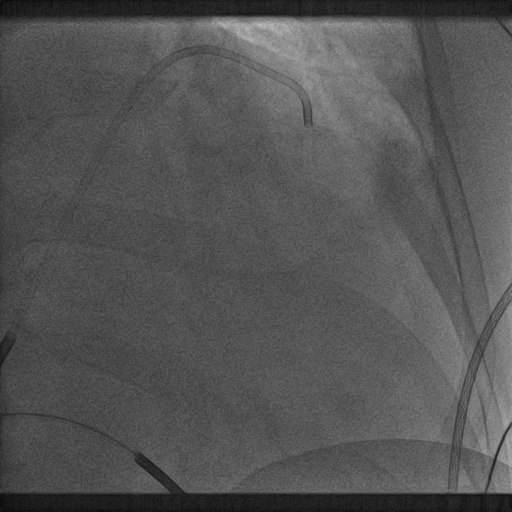

腋静脉造影

十级寻找CS

相对运动无法使鞘管深入CS

冒烟确认鞘管位置

● CS开口朝上,右房巨大,6250鞘管无法深入CS,从而无法稳定,且鞘管直接造影没法显示靶静脉情况,无法利用球囊造影,此时利用鞘中鞘,1、完成造影,2、提供支撑,为LV电极导线到达提供路径与支撑